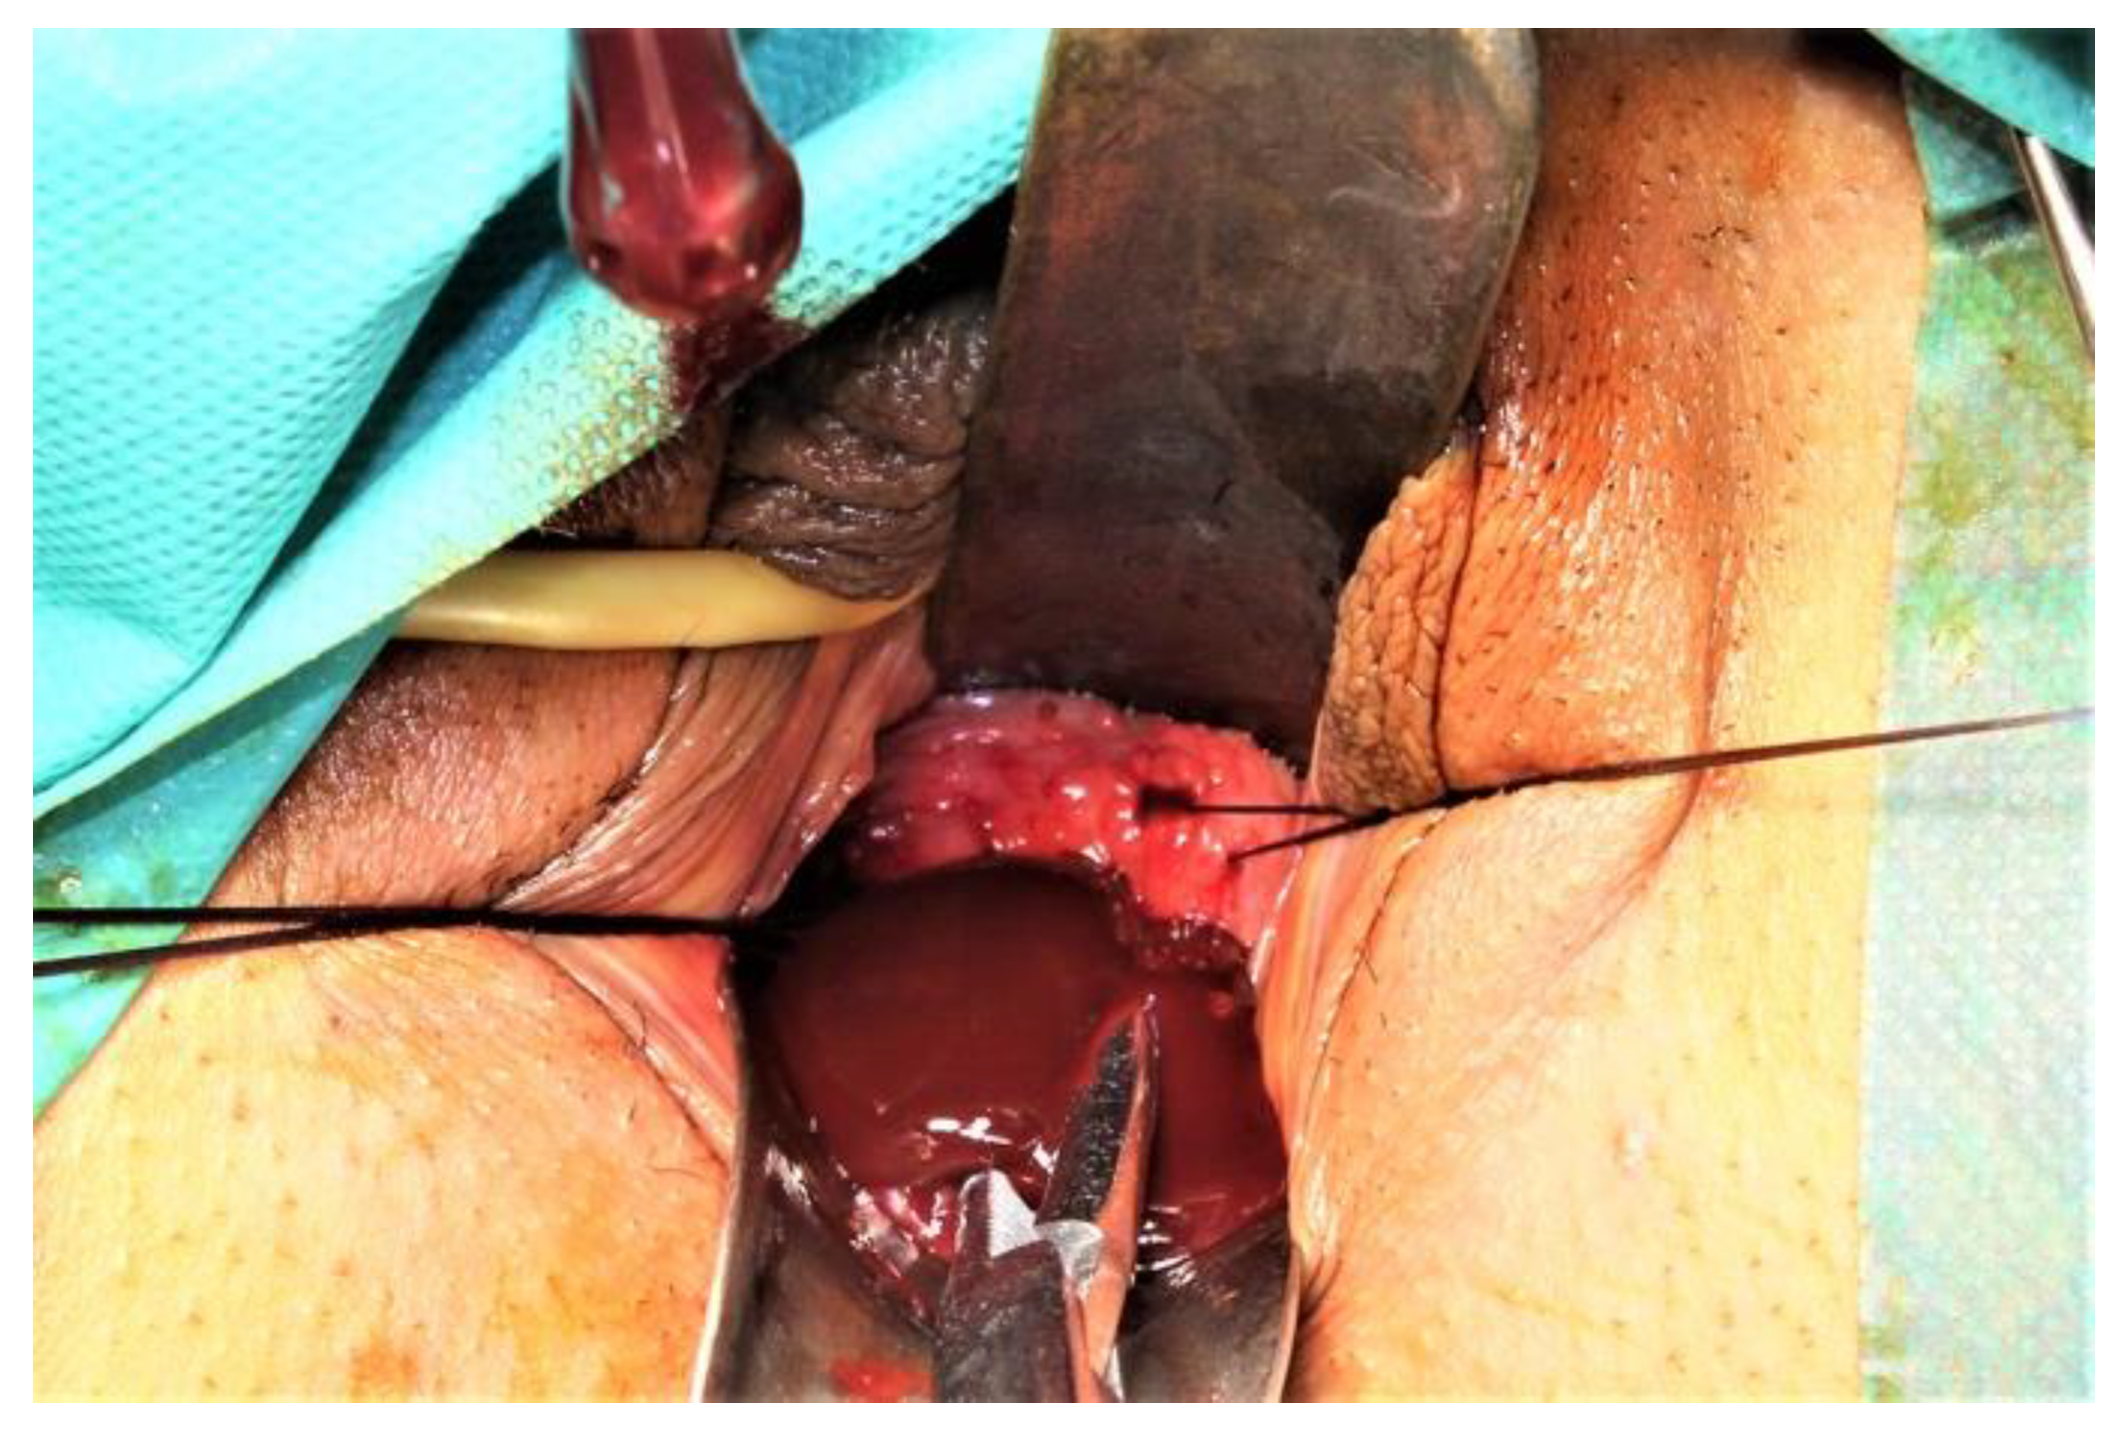

Before starting the vaginal approach, a small hymenotomy was performed to have access into the vagina. The left hemivaginal wall bulged to the midline (a schematic representation of the anomaly and its treatment is presented in Figure 3). Two traction sutures were passed through the vaginal mucosa, above and under the greatest bulging, at a 5 cm distance, and the vaginal wall was incised, followed by the evacuation of 350 mL of a “chocolate-like” content (Figure 4). An adequate excision of the vaginal wall was performed. An 18 gauge Foley catheter inflated with saline was left in the cavity for 24 h in order to facilitate drainage.

Figure 4. “Chocolate-like” (endometriotic fluid) content evacuated after vaginal wall incision.